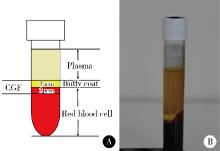

Effect of concentrated growth factors in guided tissue regeneration for the treatment of mandibular molar furcation lesions

| [5] | Xinying WANG, Xueyuan CHENG, Yong ZHANG, Fei LI, Jinyu DUAN, Jing QIAO. Therapeutic effect of concentrated growth factors combined with self-curing calcium phosphate cement on periodontal intrabony defects: Clinical and radiographic evaluation [J]. Journal of Peking University (Health Sciences), 2025, 57(1): 42-50. |

| [14] | Fei LI,Jing QIAO,Jin-yu DUAN,Yong ZHANG,Xiu-jing WANG. Effect of concentrated growth factors combined with guided tissue regeneration in treatment of classⅡ furcation involvements of mandibular molars [J]. Journal of Peking University (Health Sciences), 2020, 52(2): 346-352. |